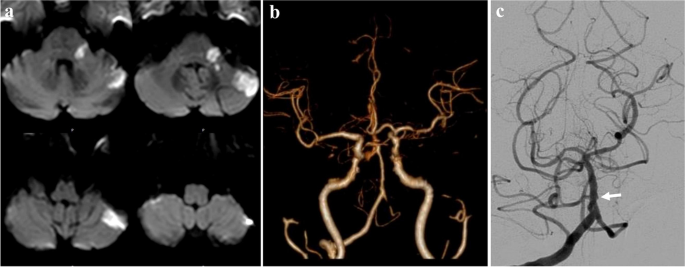

A 69-year-old woman with history of diabetes mellitus and hypertension presented with sudden vertigo, left hearing loss, and left ataxia. MRI showed hyperintensity in left brachium pontis and left superior lateral cerebellum on diffusion-weighted image (DWI) (Fig. 1a), indicating an acute infarction in left AICA territory. CTA showed the server stenosis and occlusion of left veterbral artery and absence of bilateral AICA (Fig. 1b). Digital subtraction angiography (DSA) showed occlusion from left proximal AICA (Fig. 1c). Combined with the history, the etiology was presumed as atherosclerotic occlusion of left AICA.

Diffusion-weighted image revealed acute infarction on left brachium pontis and left superior lateral cerebellum (a). Computed tomographic angiography showed the server stenosis and occlusion of left veterbral artery and the absence of bilateral anterior inferior cerebellar artery (AICA) (b). Digital subtraction angiography showed occlusion from left proximal AICA (c)